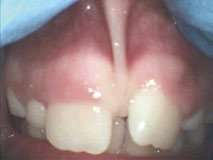

For example, Figures 2 shows the use of LightScalpel LS-1005 CO2 laser (2 watts SuperPulse Repeat Mode with F1-6 through F1-8 settings) for soft-tissue crown lengthening of the maxillary incisors and for labial frenum revision. Both procedures were performed during the same visit while the patient received local anesthesia. No sutures were placed. Figure 2 presents the self-correction of a rotated tooth #9 after the frenum revision. Laser frenectomies in Figure 3 resulted in spontaneous closure of midline diastemas.